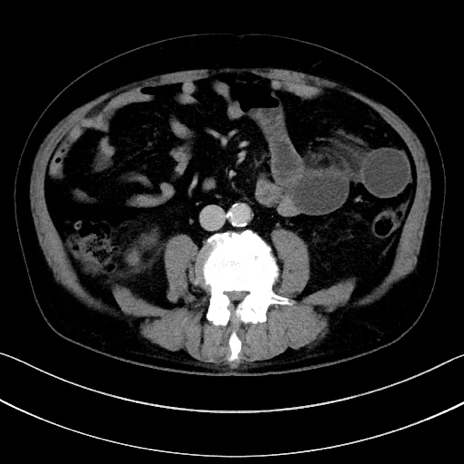

症例15(横断像)

【症例】70歳代男性

【主訴】腹痛

【現病歴】今朝から腹痛あり。全体的に痛い。特に左上の方。排ガスが今日はない。冷や汗が出る。

【既往歴】直腸癌術後

【身体所見】左側腹部〜上腹部に圧痛あり。腹膜刺激症状明らかなではない。軽度反跳痛。左下腹部に術後瘢痕あり。

【データ】WBC 7700、CRP 0.02